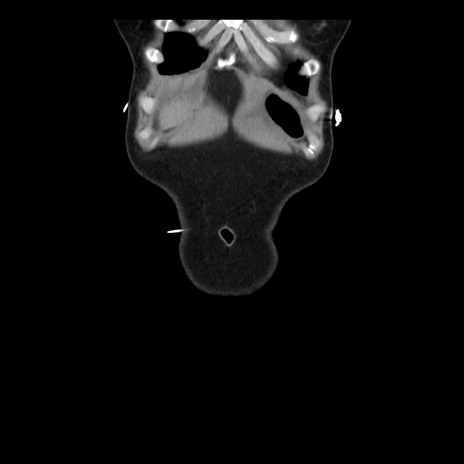

症例10(冠状断像)

【症例】 50歳代女性

【主訴】 腹痛

【現病歴】前日生レバーを食べた。今朝に排便あり。 昼前に突然発症の腹痛を生じ、当院救急外来を受診した。

【既往歴】 子宮筋腫にてで子宮全摘後

【身体所見】 意識清明、腹部:平坦、軟、下腹部やや左を中心に圧痛・反跳痛あり、筋性防御あり

【データ】WBC 7800、CRP 0.07